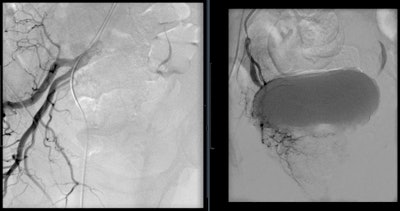

Prostate artery embolization is a noninvasive procedure that can bring long-term relief from symptoms caused by an enlarged prostate. This procedure works by closing the blood supply to the prostate, and, as a result, the prostate shrinks in size, reducing blockages and improving the symptoms.

Prostatic hematuria is usually associated with BPH, iatrogenic urological trauma, or radiation therapy. Traditionally, it is treated conservatively with increased fluid intake, indwelling catheterization with bladder irrigation, and medical therapy. However, when these interventions fail, refractory hematuria is life-threatening. PAE has been shown to be an option for these patients. Although distinct prostatic hemorrhage is rarely seen on angiography, PAE is successful by obtaining complete arterial occlusion. By utilizing a superselective approach, control or cessation of hematuria within one to three days is achieved in 83% to 100% of patients.

Although the complications are minimal, PAE has adverse effects postprocedure. For patients without indwelling catheters, urethral burning during voiding and frequent urination have been the most common symptoms after PAE. However, these effects usually resolve within a week and can be treated with nonopioid analgesic medications. More serious complications are associated with nontarget embolization to the bladder, rectum, and penis. Ischemia to these organs is always possible and must be avoided through proper mapping via CBCT, microcatheterization for distal embolization, and calibrated microspheres for predictable embolization.